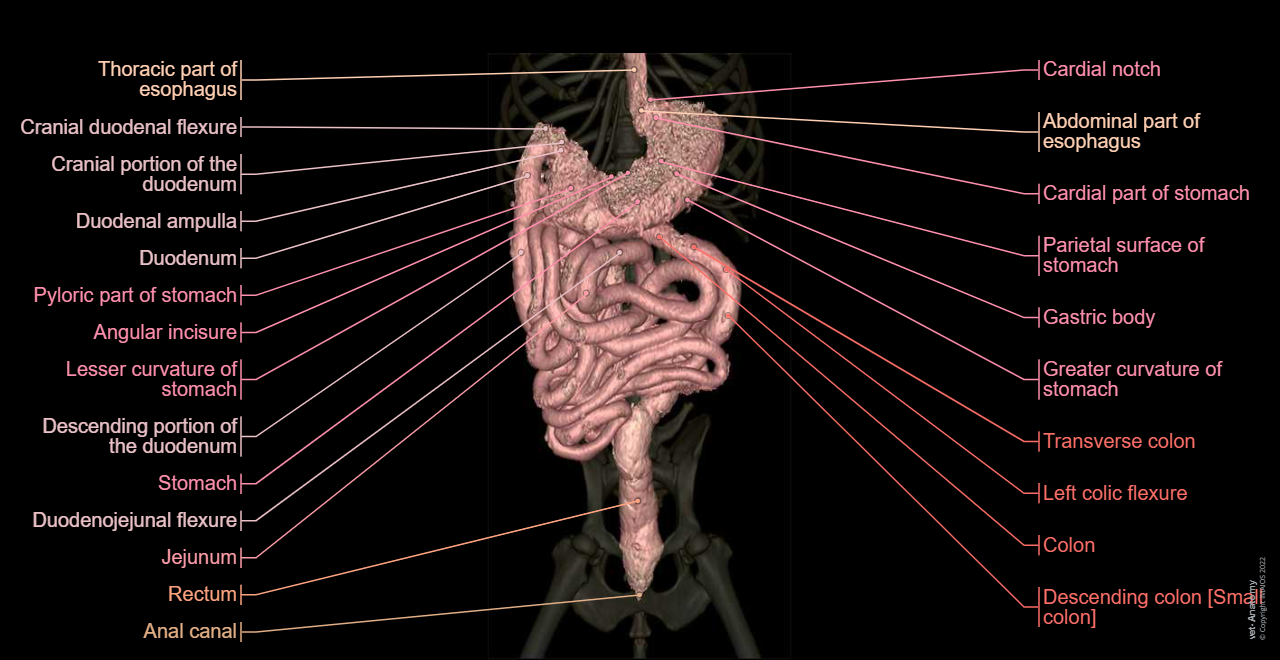

Anatomy of the male canine abdomen and pelvis on CT imaging: Alimentar canal, Stomach, Colon

Dog - Digestive system - 3D - Anatomy: Stomach, Duodenum, Jejunum, Ileum, Small intestine, Large intestine, Colon, Rectum

Dog